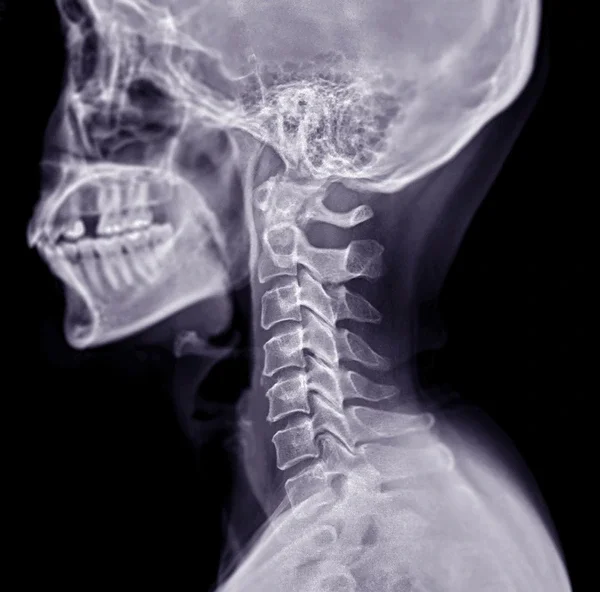

At The Catalyst Spine Co., we provide safe, evidence-informed chiropractic care for patients recovering from auto accidents and other personal injuries. Our goal is to reduce pain, restore function, and help you return to normal life as quickly as possible.

Imaging referrals when clinically indicated

Whether you’re experiencing neck pain, back pain, headaches, or soft tissue injuries following an accident, our care focuses on restoring mobility, reducing inflammation, and supporting your body’s healing process.